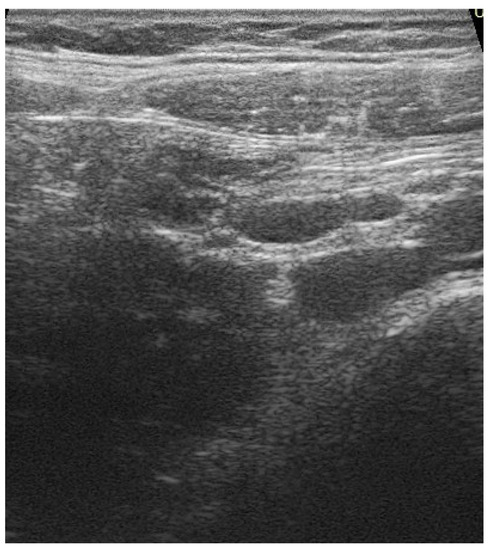

2. Case History

2.1. Differential Diagnosis, Investigations and Treatment